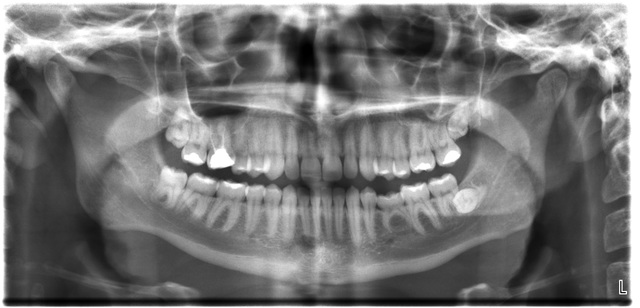

Radiografia dental

HISTORIA DE LA RADIOLOGÍA DENTAL